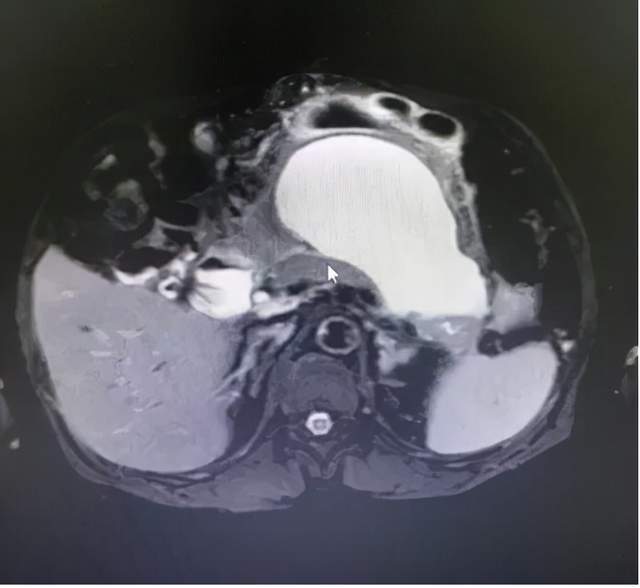

9月10日 , 在山西省汾阳医院消化内镜团队与麻醉科共同协作下 , 成功为一例急性胰腺炎后胰腺假性囊肿合并感染的患者实行了超声内镜(EUS)引导下胰腺假性囊肿穿刺引流术+ERCP(经内镜逆行胰胆管造影)胰管支架置入术 。

患者 , 中年男性 , 2020年6月20日 , 因急性重症胰腺炎住院 , 7月28日因并发假性囊肿行外科胰腺假性囊肿开窗引流 , 胰周坏死组织清创 , 脓肿置换冲洗引流 , 2021年4月28日 , 拔除腹腔引流管 。 入院前20天再次出现腹痛 , 伴发热 。 入院后查炎症指标明显增高 , 考虑假性囊肿合并感染 , MRCP提示胰体尾部胰管扩张 , 提示胰管引流不畅 , 遂决定行ERCP胰管支架置入术+EUS引导下胰腺假性囊肿穿刺引流术 。